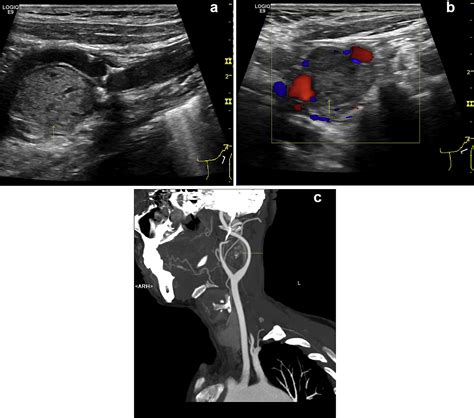

• Imaging studies: Various imaging techniques are used to visualize the tumor and determine its size, location, and extent. Common imaging studies include:

Ultrasound Uses sound waves to create images of the tumor and can assess blood flow within the tumor.

Angiography Involves injecting a contrast dye into the blood vessels to visualize the tumor's vascular supply and plan for surgical intervention.